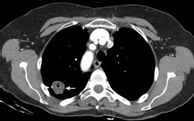

良性病因 - 良性肺结节的常见原因包括感染性肉芽肿(如图4)和良性肿瘤,如肺错构瘤(如图5)。不太常见的原因包括血管(如图6)和炎症性病变。

图5 肺错构瘤(软骨、脂肪等长错了位置)